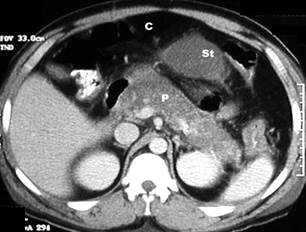

Figure 15 – CT scan in acute pancreatitis

Post Contrast CT findings reveal diffusely enlarged pancreas with low density from oedema. C – colon, St – stomach,

P – pancreas